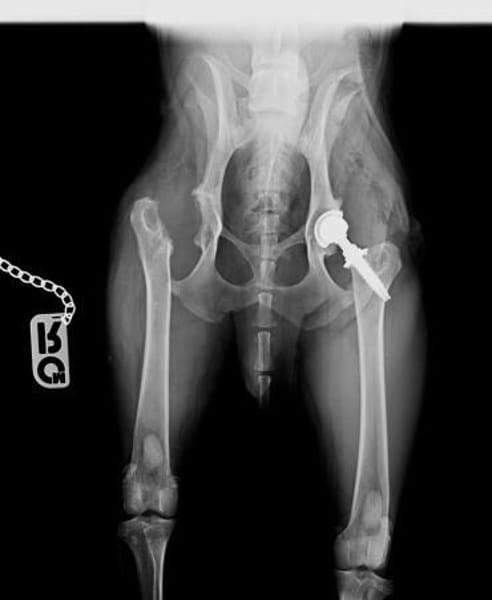

Bekannte Krankheiten: taub, künstliche Hüfte

Teddy hat inzwischen 2 große Operationen hinter sich: eine Femurkopfresektion auf der einen und ein künstliches Hüftgelenk auf der anderen Seite. Er lebt nun endlich schmerzfrei, moderate Spaziergänge sind sehr gut mit ihm möglich